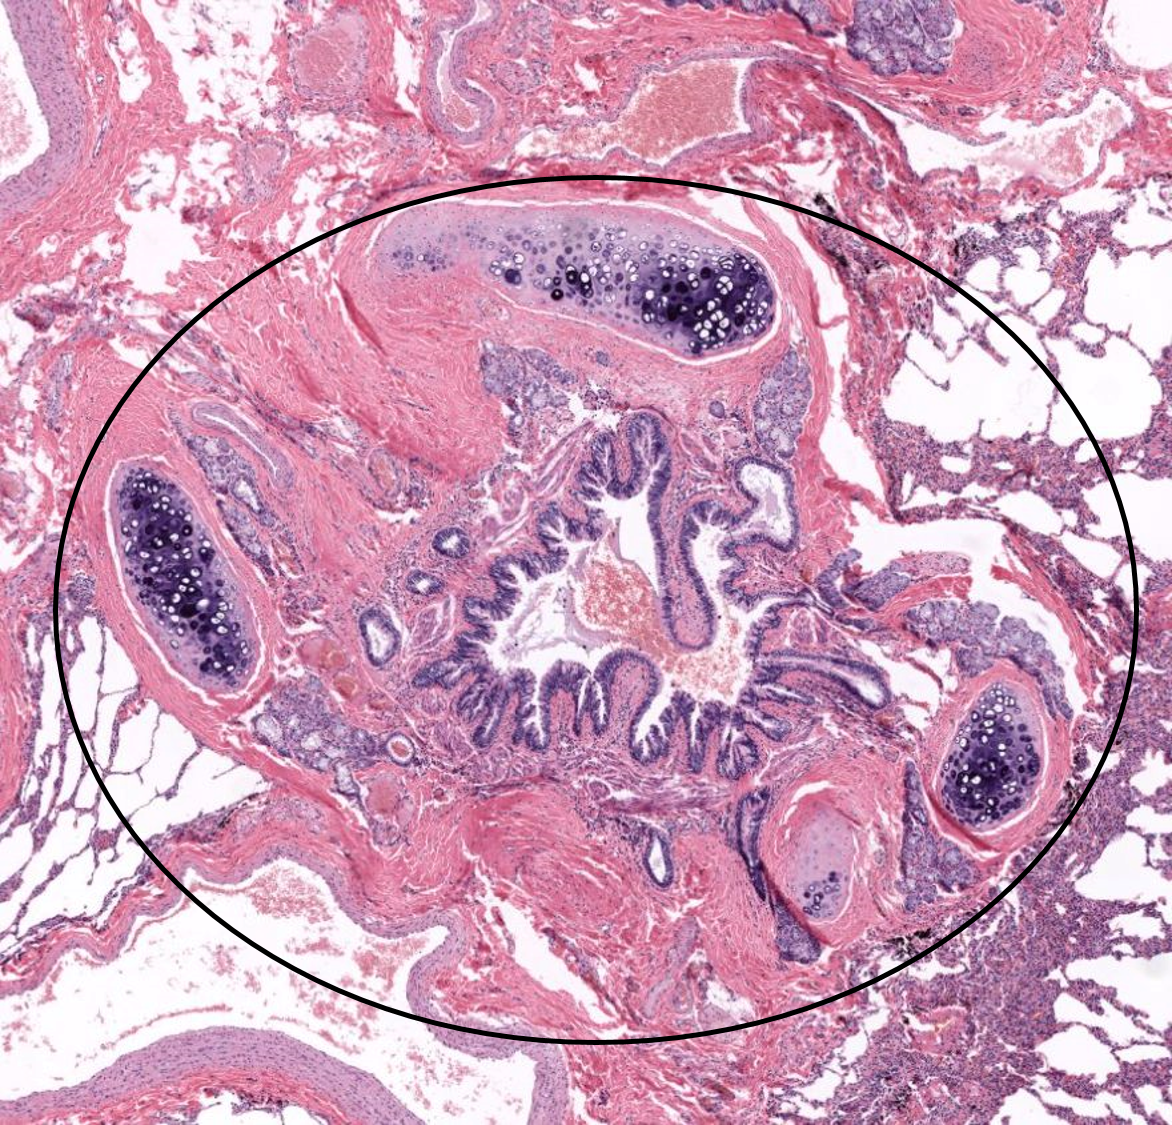

Pulmão

Brônquio

1: Saco alveolar

2: Alvéolo